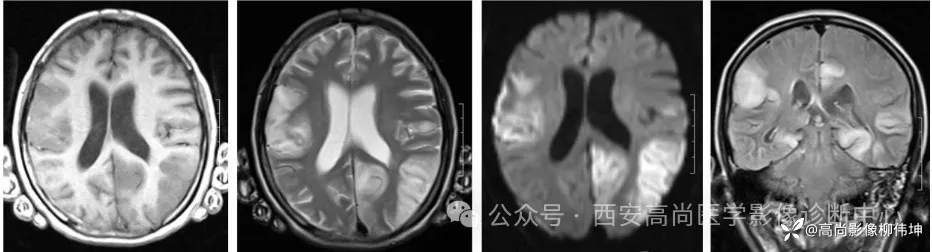

03 影像表现

(2)胼胝体DWI高信号

部分患者在病程早期仅出现胼胝体的DWI高信号,提示胼胝体联络纤维和皮质下弓形纤维具有类似的易受累性。需要和可逆性胼胝体压部脑病、Marchiafava-Bignami综合征进行鉴别。

(3)对称性脑白质病变

显著累及放射冠和半卵圆中心部位的白质病灶。

04 鉴别诊断

克雅氏病:又称皮质-纹状体-脊髓变性。临床上以快速进行性痴呆、肌阵挛、共济失调为主要表现。典型影像学表现为对称或非对称性皮层和(或)基底节区受累,通常不累及中央回,扣带回、角回、楔前叶、额上回及纹状体为主要受累部位,DWI信号随病情进展信号增高,可持续数周,晚期消失,晚期脑萎缩改变。

皮层下动脉硬化性脑病(Binswanger病):本病为老年人在脑动脉硬化基础上,大脑半球白质弥漫性脱髓鞘性脑病。影像上表现为脑室周围白质与半卵圆中心显示散在或融合性病变区,T1WI呈低信号,T2WI呈高信号。重度与中度显示脑室扩大,腔隙性脑梗死显影清晰,FLAIR上脱髓鞘斑块及腔隙性脑梗死表现为高信号常伴有脑萎缩。